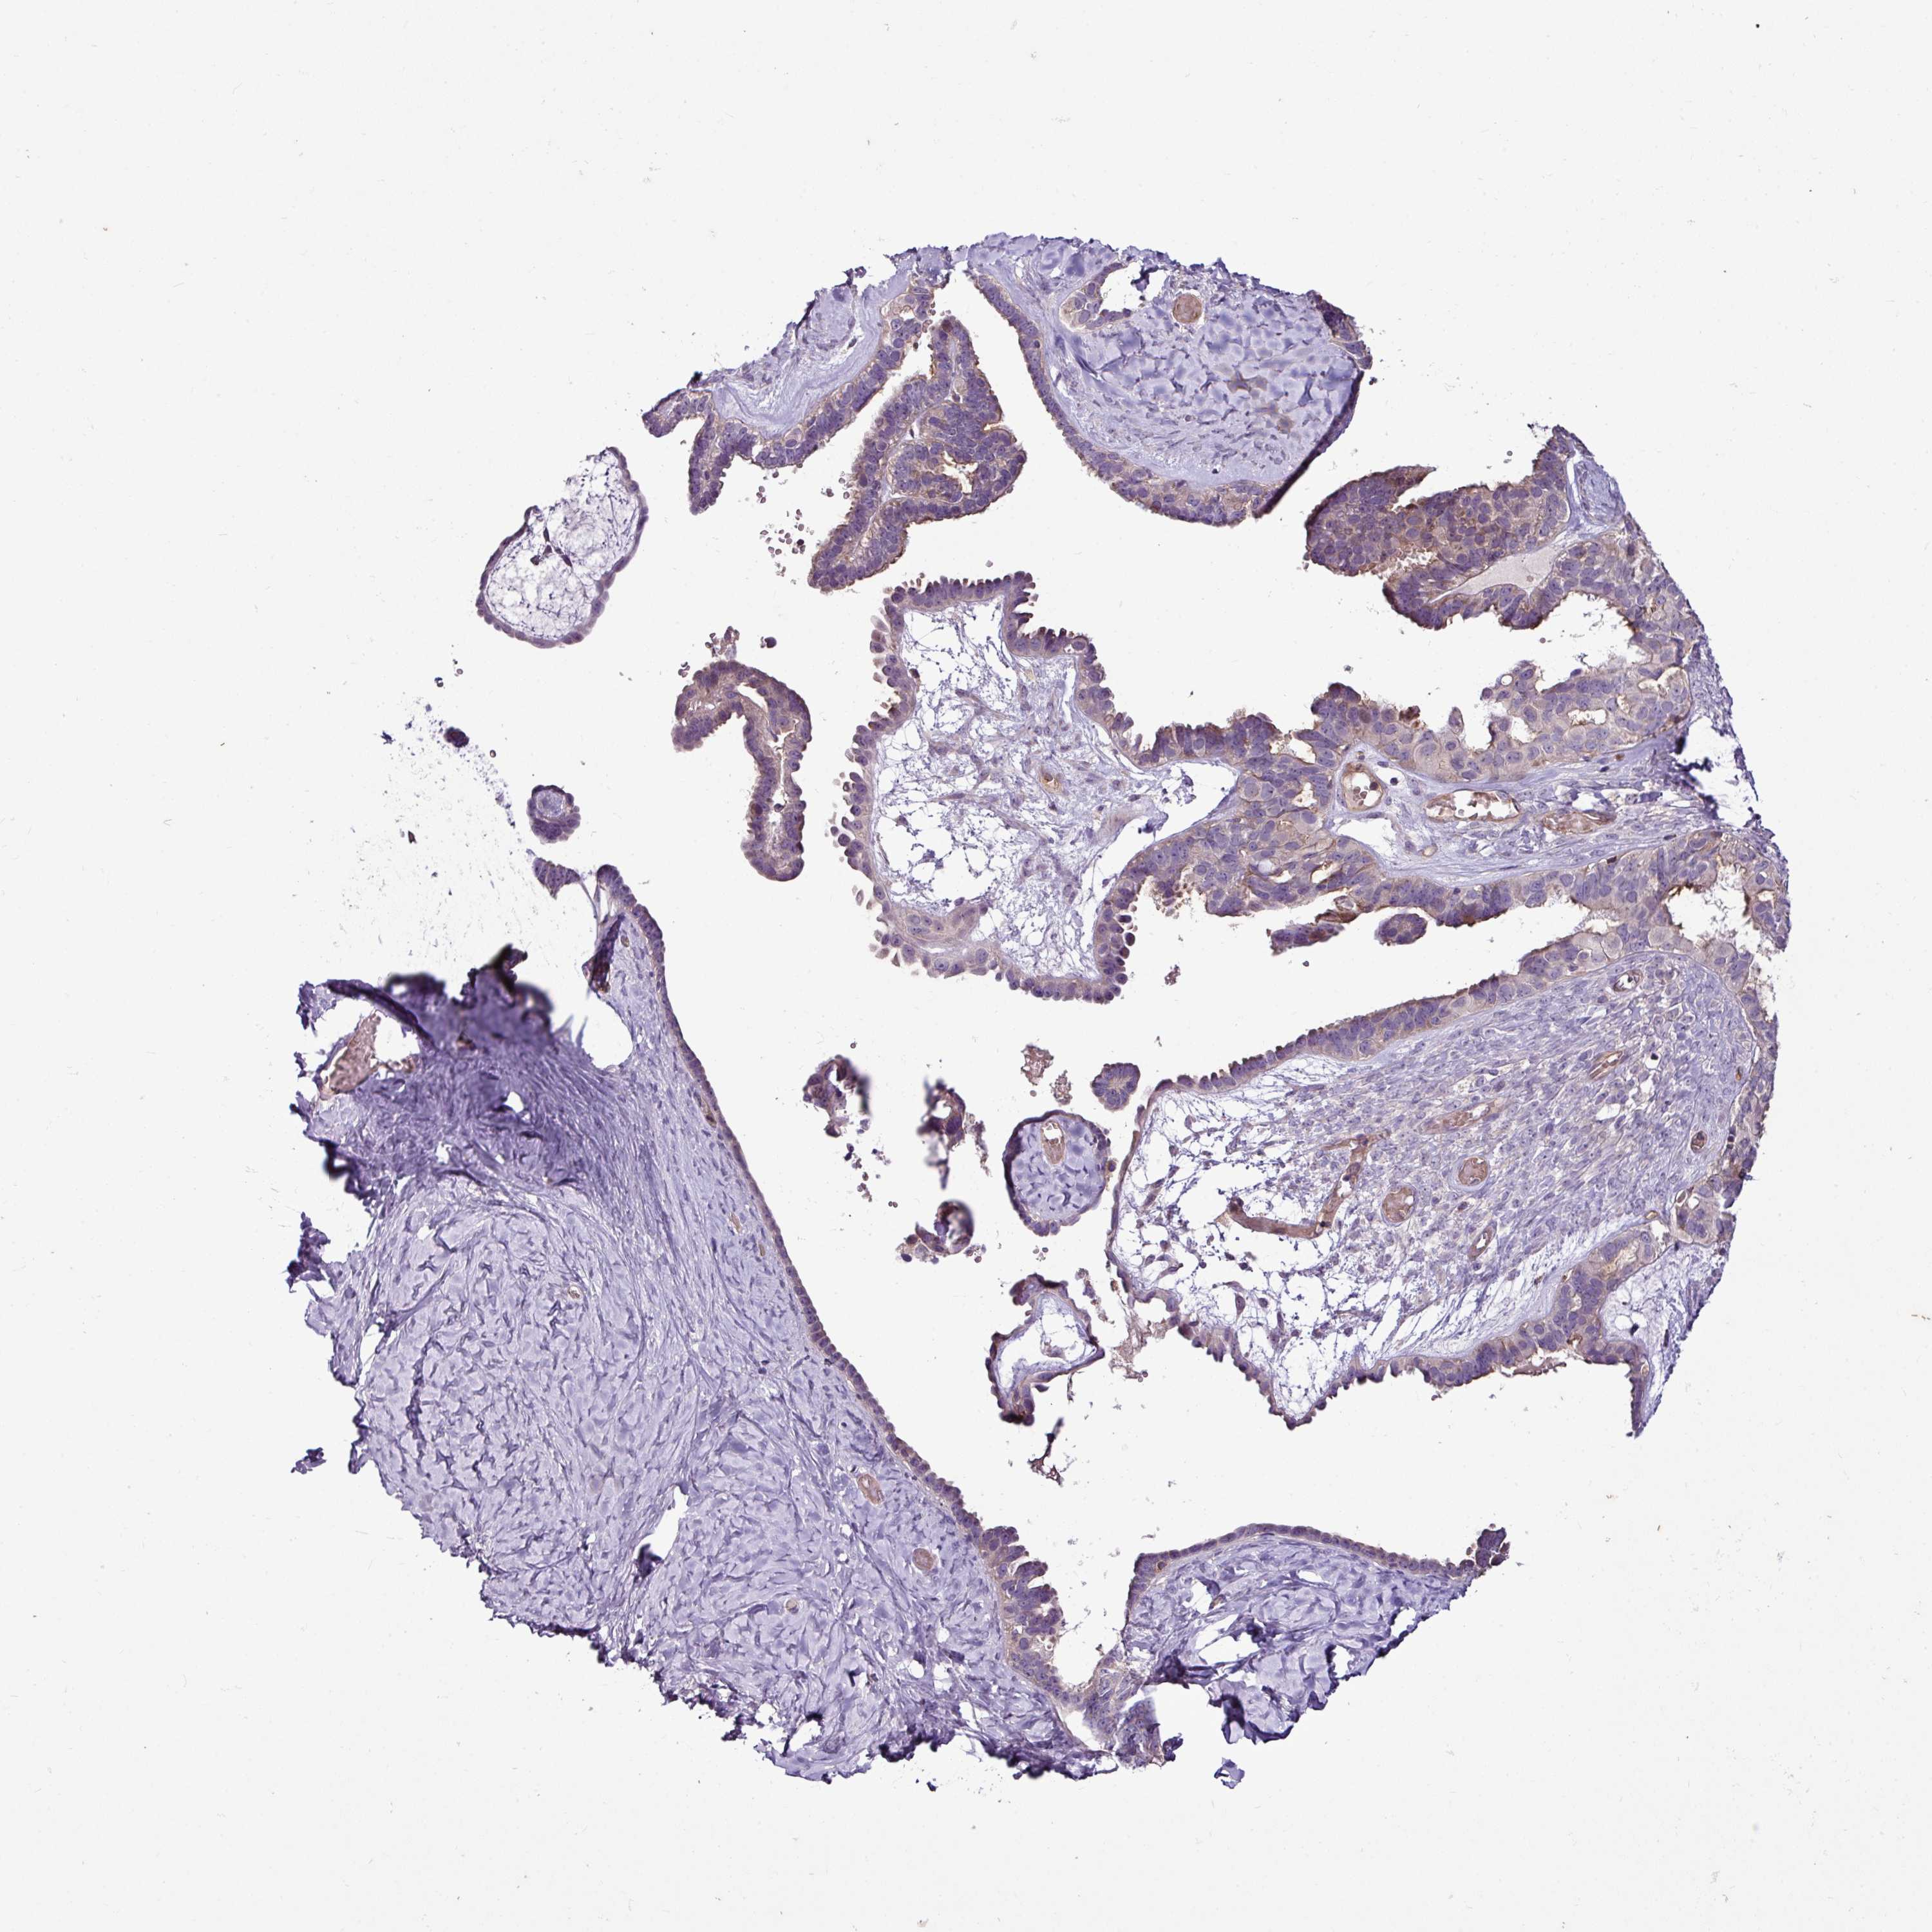

OVARIAN CANCER - Protein expressioni

A mouse-over function shows sample information and annotation data. Click on an image to view it in a full screen mode. Samples can be filtered based on level of antibody staining by selecting one or several of the following categories: high, medium, low and not detected. The assay and annotation is described here.

Note that samples used for immunohistochemistry by the Human Protein Atlas do not correspond to samples in the TCGA dataset.

Antibody stainingi

Antibody staining in the annotated cell types in the current human tissue is reported as not detected, low, medium, or high, based on conventional immunohistochemistry profiling in selected tissues. This score is based on the combination of the staining intensity and fraction of stained cells.

Each image is clickable and will lead to virtual microscopy that enables deeper exploration of all samples and also displays staining intensity scores, fraction scores and subcellular localization as well as patient and tissue information for each sample.

Antibody HPA054267

Staining

High

Medium

Low

Not detected

Intensity

Strong

Moderate

Weak

Negative

Quantity

>75%

75%-25%

<25%

None

Location

Nuclear

Cytoplasmic/membranous

Cytoplasmic/membranous,nuclear

Cystadenocarcinoma, serous, NOS

Cystadenocarcinoma, mucinous, NOS

Adenocarcinoma, NOS

Carcinoma, endometroid